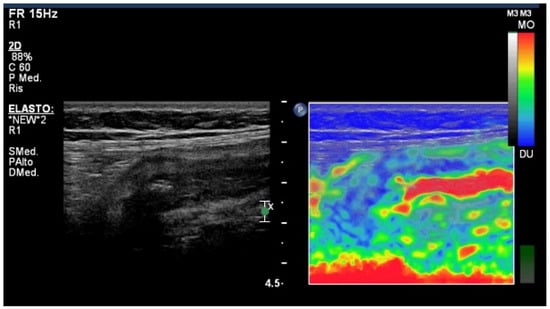

4. Elastography Imaging Techniques

- Fraquelli, M.; Branchi, F.; Cribiù, F.M.; Orlando, S.; Casazza, G.; Magarotto, A.; Massironi, S.; Botti, F.; Contessini-Avesani, E.; Conte, D.; et al. The Role of Ultrasound Elasticity Imaging in Predicting Ileal Fibrosis in Crohn’s Disease Patients. Inflamm. Bowel Dis. 2015, 21, 2605–2612. [Google Scholar] [CrossRef]

- Baumgart, D.C.; Müller, H.P.; Grittner, U.; Metzke, D.; Fischer, A.; Guckelberger, O.; Pascher, A.; Sack, I.; Vieth, M.; Rudolph, B. US-based Real-time Elastography for the Detection of Fibrotic Gut Tissue in Patients with Stricturing Crohn Disease. Radiology 2015, 275, 889–899. [Google Scholar] [CrossRef]

- Re, G.L.; Picone, D.; Vernuccio, F.; Scopelliti, L.; Di Piazza, A.; Tudisca, C.; Serraino, S.; Privitera, G.; Midiri, F.; Salerno, S.; et al. Comparison of US Strain Elastography and Entero-MRI to Typify the Mesenteric and Bowel Wall Changes during Crohn’s Disease: A Pilot Study. Biomed. Res. Int. 2017, 2017, 4257987. [Google Scholar] [CrossRef]

- Serra, C.; Rizzello, F.; Pratico’, C.; Felicani, C.; Fiorini, E.; Brugnera, R.; Mazzotta, E.; Giunchi, F.; Fiorentino, M.; D’errico, A.; et al. Real-time elastography for the detection of fibrotic and inflammatory tissue in patients with stricturing Crohn’s disease. J. Ultrasou. 2017, 20, 273–284. [Google Scholar] [CrossRef]

- Chen, Y.; Mao, R.; Li, X.; Cao, Q.; Chen, Z.; Liu, B.; Chen, S.; Chen, B.; He, Y.; Zeng, Z.; et al. Real-Time Shear Wave Ultrasound Elastography Differentiates Fibrotic from Inflammatory Strictures in Patients with Crohn’s Disease. Inflamm. Bowel Dis. 2018, 24, 2183–2190. [Google Scholar] [CrossRef]

- Lu, C.; Gui, X.; Chen, W.; Fung, T.; Novak, K.; Wilson, S.R. Ultrasound Shear Wave Elastography and Contrast Enhancement: Effective Biomarkers in Crohn’s Disease Strictures. Inflamm. Bowel Dis. 2017, 23, 421–430. [Google Scholar] [CrossRef]

- Orlando, S.; Fraquelli, M.; Coletta, M.; Branchi, F.; Magarotto, A.; Conti, C.B.; Mazza, S.; Conte, D.; Basilisco, G.; Caprioli, F. Ultrasound Elasticity Imaging Predicts Therapeutic Outcomes of Patients with Crohn’s Disease Treated with Anti-Tumour Necrosis Factor Antibodies. J. Crohn’s Coli. 2018, 12, 63–70. [Google Scholar] [CrossRef]